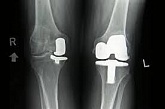

Еndoprosthesis of knee joint

In the late stages of arthrosis of the knee joint, accompanied by a pronounced restriction of the volume of movements, constant intense pain, deformity of the limb, the only way to recover is to replace the affected joint with an artificial joint - arthroplasty.

This method allows you to return the correct form of the limb, the full volume of movements in the joint, relieve the constant pain and crunch during movements and, as a result, significantly improve the patient's quality of life.

Below are presented X-ray photographs and photographs, illustrating the amount of motion in the affected joint before and after surgery.